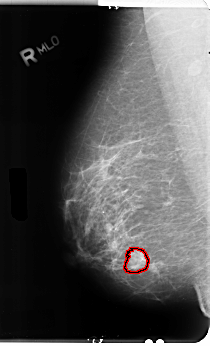

B_3106_1.RIGHT_MLO

FILE: B_3106_1.RIGHT_MLO.OVERLAY

TOTAL_ABNORMALITIES 1

ABNORMALITY 1

LESION_TYPE MASS SHAPE ROUND MARGINS SPICULATED

ASSESSMENT 4

SUBTLETY 4

PATHOLOGY MALIGNANT

TOTAL_OUTLINES 1

BOUNDARY